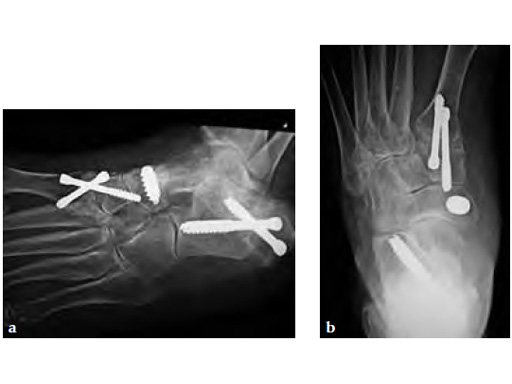

A medializing calcaneal osteotomy was performed and fixed with two 6.5 mm HCS, a flexor hallucis longus transfer to her navicular is secured with an interference 7 mm screw and a lapidus procedure fixed with two crossing 4.5 HCS (see Fig 2a-b).

Progressive weight bearing was permitted at 8 weeks and UCBL was advised until the fourth postoperative month (see Fig 3a-b).